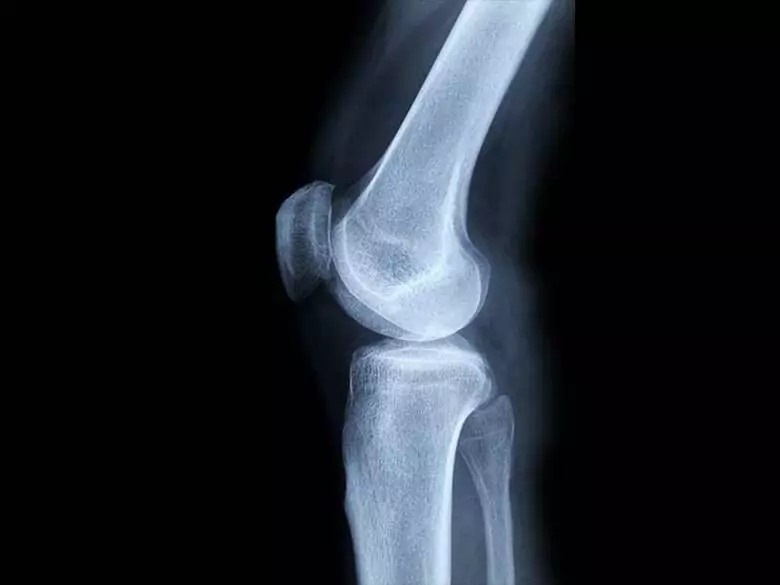

Pomimo, iż nie jest najczęściej występującą odmianą nowotworu, jest chorobą bardzo złośliwą, szybko rozwijającą się i dającą przerzuty. Nowotwór złośliwy kości o charakterze pierwotnym jest trudny do zdiagnozowania. Ze względu na jego umiejscowienie oraz znane przyczyny, nie można wskazać działań prewencyjnych.